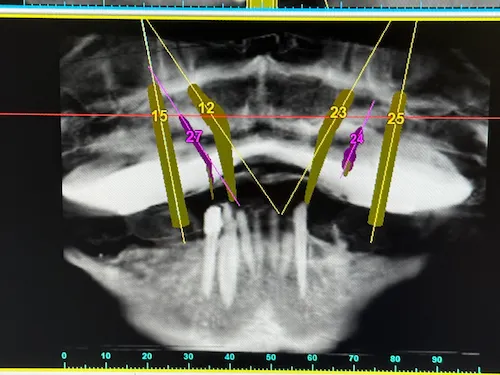

Unter Einsatz der SIMPLANT® Planungssoftware kann der Implantolgoe die optimalen Implantatpositionen vorab am Computer planen, wobei sämtliche Planungsdaten anschließend in die Herstellung einer individuellen Bohrschablone einfließen. Die Bohrschablone ermöglicht ein punktgenaues, schonendes Einsetzen der Implantate an den zuvor geplanten Positionen, minimiert das Verletzungsrisiko und beschleunigt letztendlich die Heilung.

Das Behandlung mit Camfour™ sieht 4-6 Implantate je Zahnbogen vor. Meist reichen jedoch 4 Implantate aus. Die speziell für diesen Zweck ausgelegten Zahnimplantate werden mit einem Winkel von bis zu 45° in den Knochen eingebracht. Durch die geneigten Implantate ist der Spezialist für Implantologie unabhängiger vom noch vorhandenen Knochenvolumen und kann ohne einen vorherigen Knochenaufbau implantieren. Wichtig ist, dass die Zahnimplantate bereit unmittelbar nach Einsetzen stabil im Kieferknochen sitzen. Dies wird durch das spezielle All-on-4 ® / All-on-6 ®- Implantationsverfahren sichergestellt. Eine hohe „Primärstabilität“ der Implantate ist die wichtigste Grundvoraussetzung für eine Sofortversorgung mit Zahnersatz noch am gleichen Tag.

Bevor an einen operativen Eingriff gedacht werden kann, stehen als erstes Röntgenbilder mithilfe der Digitalen Volumentomographie auf dem Programm. Hier sind die Überreste in Ober-und Unterkiefer gut zu sehen, vor allem aber die Positionen der abgebrochenen Zahnwurzeln. Auf Basis der Bilder können die Positionen für die insgesamt 8 Implantate auf den Millimeter genau geplant werden: Unser Patient wird jeweils 4 Implantate im Ober-und Unterkiefer erhalten, die im Nachgang jeweils mit einem festsitzenden Zahnersatz versorgt werden. Die Einheilphase dauert zwischen 4 und 6 Monate, prognostiziert Dr. Mintert, der Spezialist für Implantate in der ZPK Herne.

Implantatplanung - Oberkiefer - All-on-Four Konzept

Implantatplanung - Unterkiefer - All-on-Four Konzept